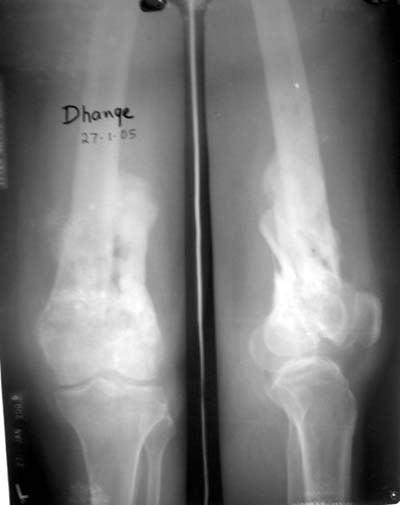

Before the CT and MRI era, we were treating the fractures with study of the Xrays alone. Such fractures with skeletal traction followed by non wtbearing mobilisation used to yield a fairly good range of movements. The CT gives a real ghastly picture of not so bad looking plain Xrays. I think this case needs traction to start with to correct the flexion deformity which probably will be achieved in 2 weeks time or less. We can then reassess the case with fresh Xrays. If possible one should try and fix the fragments to get some alignment. But the fixation should be stable enough to be able to mobilise the joint. Otherwise the traction can be continued for another 2 weeks to make the fracture sticky and then mobilise. We could get about 70 to 80* movements in spite of such communition. I am enclosing an Xray of a patient who is walking independantly and has 0 to 80* movemnts of the knee for the last one year